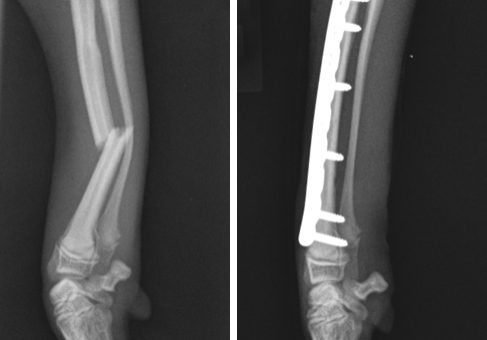

Depending on the type of fracture, X-rays or a CT scan are performed to assess the broken bone and plan the treatment. Many fractures occur as a result of significant trauma, such as being hit by a car, and for these patients it is important that any additional life-threatening injuries are recognised and managed promptly.

Some fractures, especially in very young animals, can be treated using fibreglass casts. Unlike humans, dogs and cats cannot be relied on to rest the limb properly, and any bandaging has the potential to cause serious complications. As a result, most animals are best treated with an operation in which the broken bones are re-aligned and stabilised. Options for stabilising the bones include bone plates and screws, pins that are placed inside the bone, or external frames that are connected to the bone using pins going through the skin. Some fractures are relatively straightforward to manage and others are very complex, necessitating considerable orthopaedic instrumentation, implants and expertise.

Depending on the type of fracture, repair may involve the placement of pins, screws, interlocking nails, or bone plates.